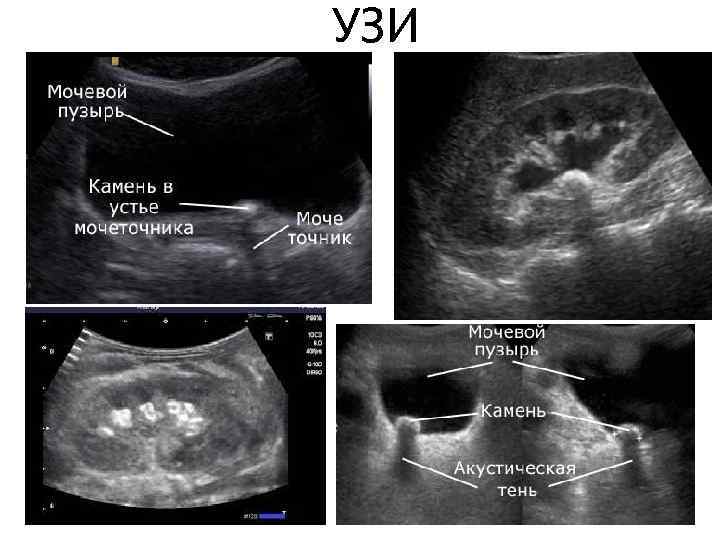

Диагностика • Анализ анамнеза заболевания и жалоб. • Анализ анамнеза жизни. • Данные врачебного осмотра (положительный симптом поколачивания — боль при легких ударах в поясничной области). • Анализ крови — сдвиг лейкоцитарной формулы влево, повышение СОЭ (скорость оседания эритроцитов, неспецифический признак воспаления). • Анализ мочи — появляются эритроциты, единичные цилиндры (своего рода слепки канальцев почек, которые состоят из свернувшихся в кислой среде мочи белков и других компонентов, важный признак почечной патологии) и соли, лейкоцитурия (обнаружение лейкоцитов в моче — признак воспаления) Эндоскопические методы: • Цистоскопия • УЗИ Рентгенологические методы: • обзорная рентгенография брюшной полости • экскреторная урография • Динамическая сцинтиграфия • Компьютерная томография с контрастированием

УЗИ